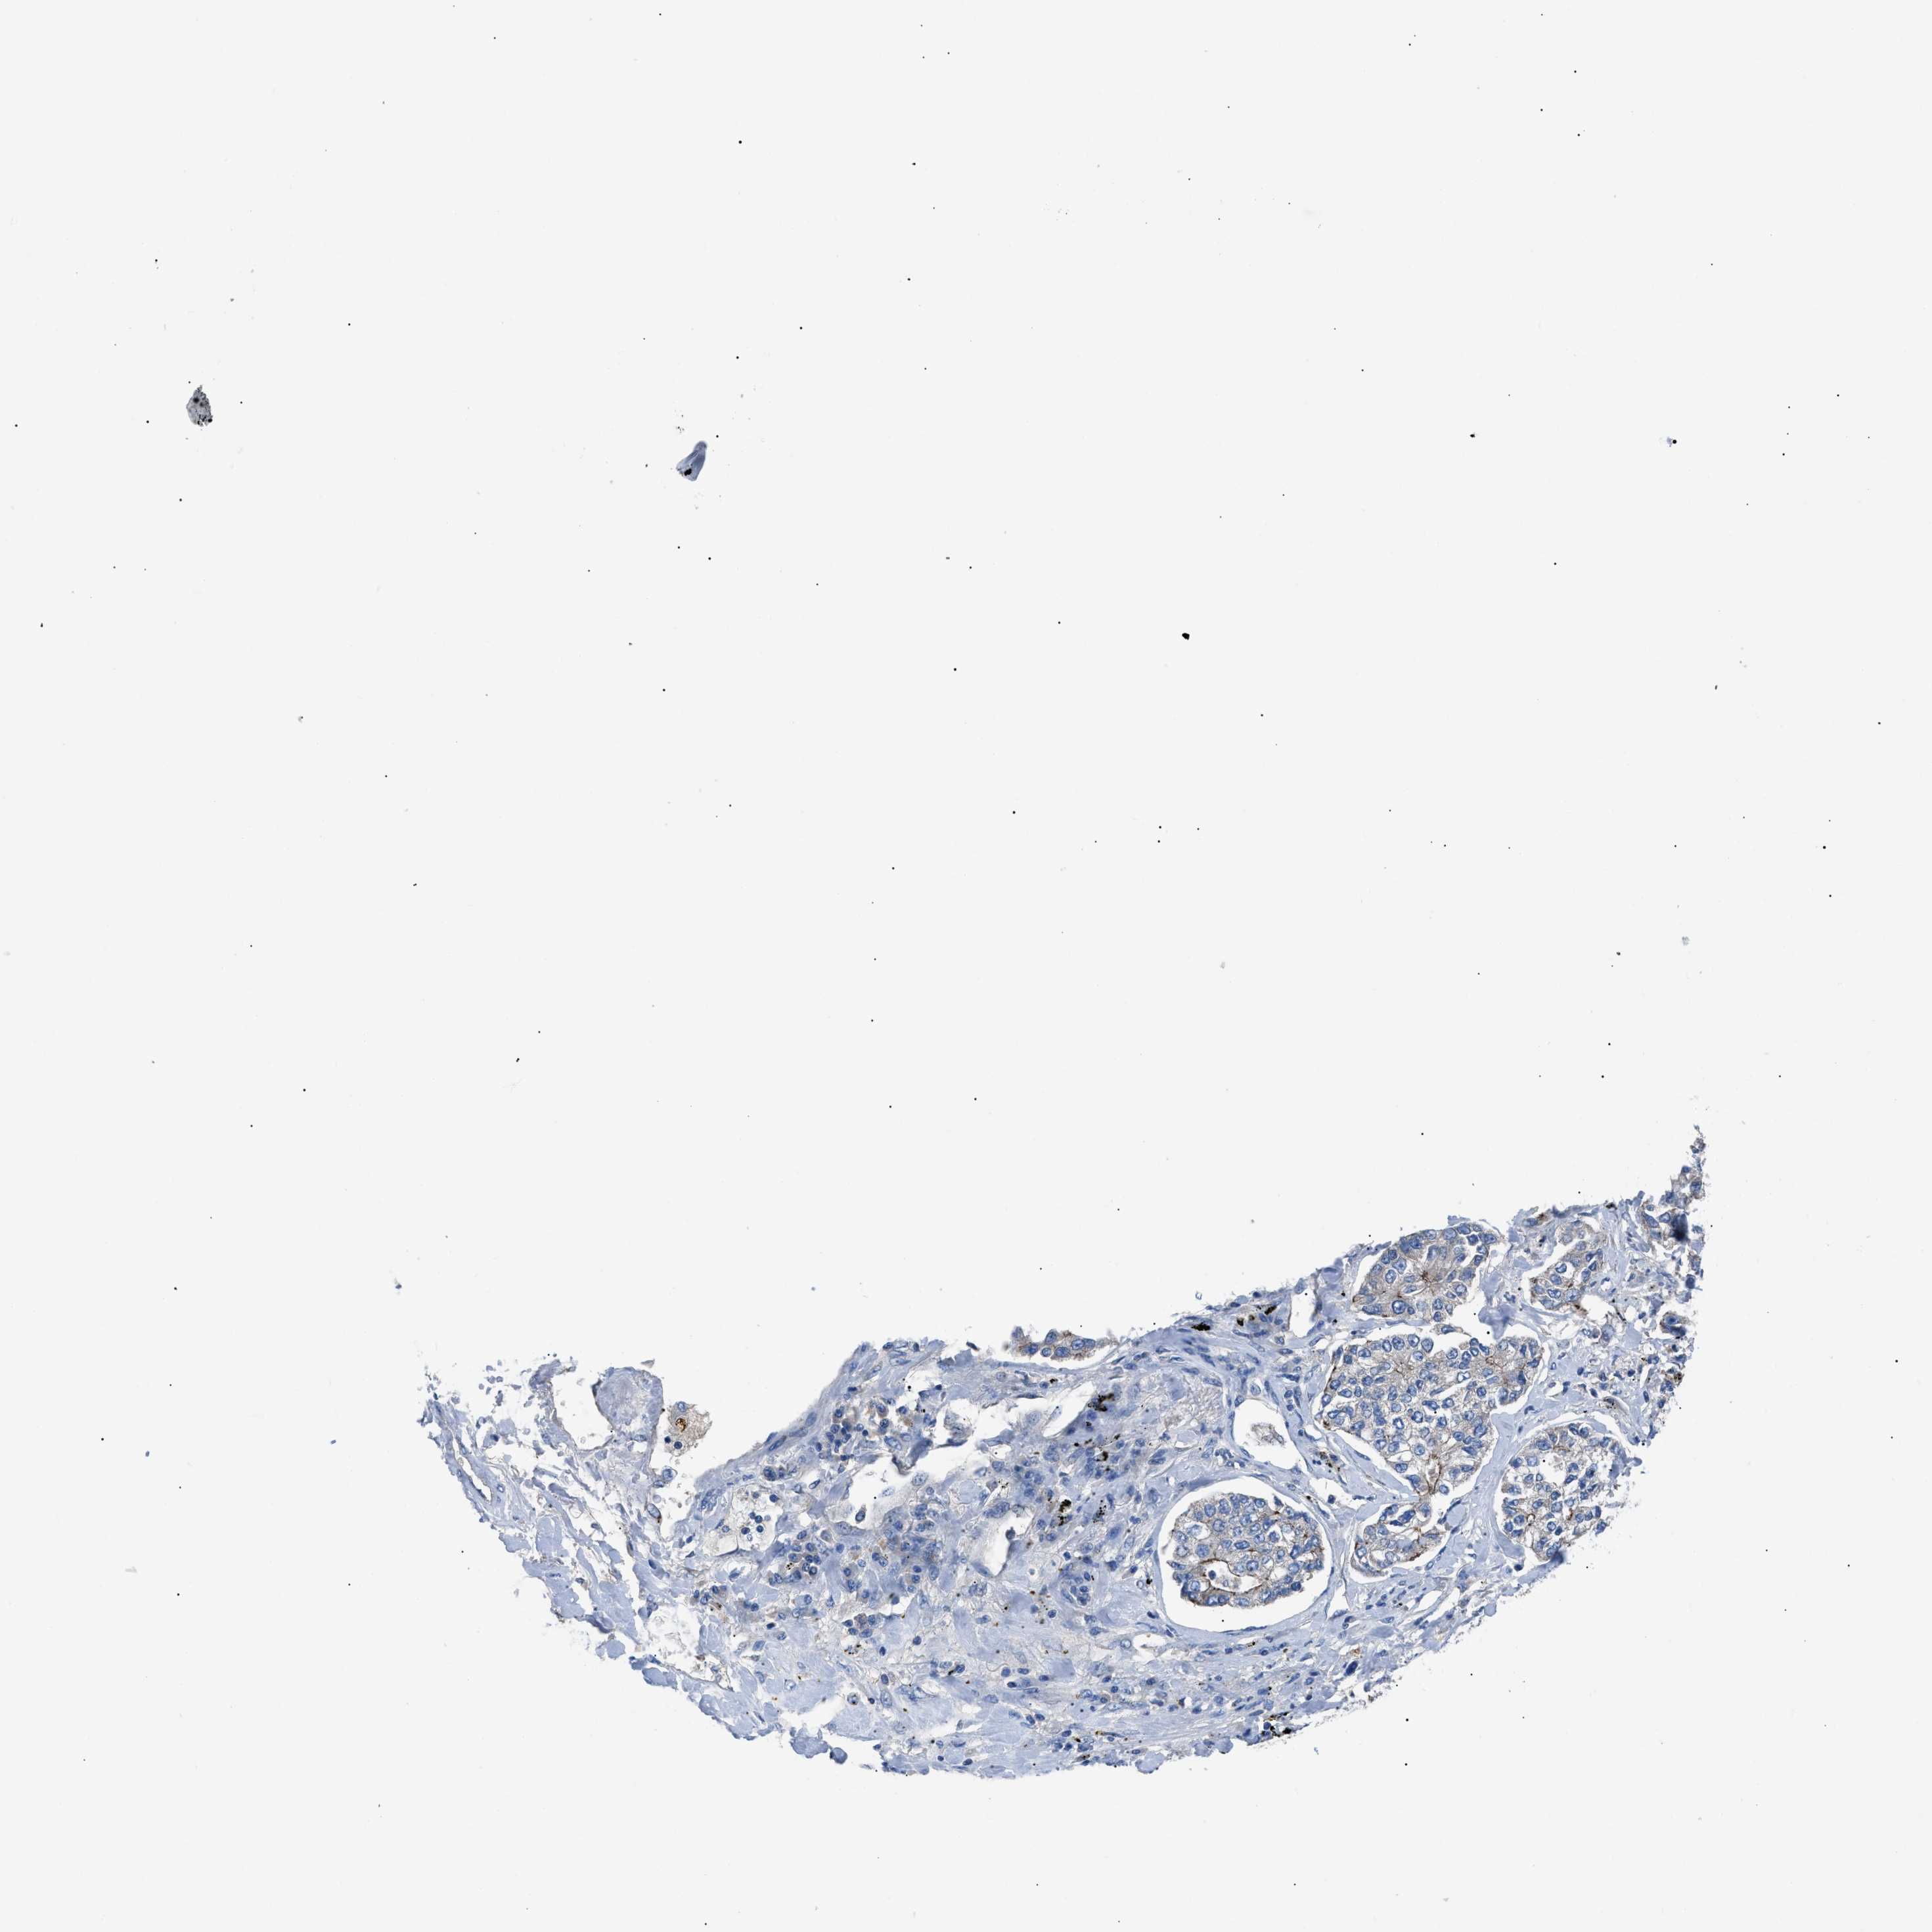

CANCER LUNG CANCER Show tissue menu

Lung cancer

Human cancer

Lung adenocarcinoma

Lung squamous cell carcinoma